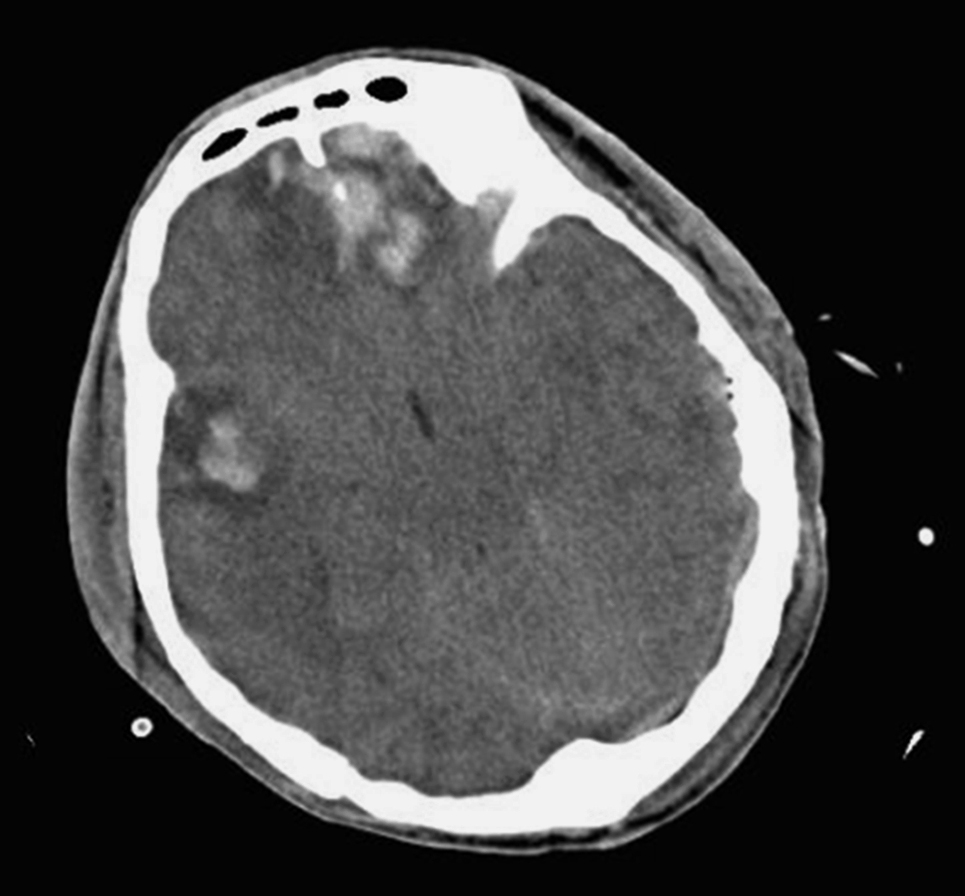

脑内血肿颅内高压:明显的头痛、恶心、呕吐及生命体征变化等。局灶性症状:额叶底部和颞叶前部脑内血肿,常伴有严重的脑挫裂伤和脑干损伤,多呈持续昏迷状态。若血肿破入脑室,患者意识障碍更加明显;位于运动区附近的血肿,可出现偏瘫、失语和局灶性癫痫。顶叶血肿可出现偏侧感觉障碍。脑疝的症状:瞳孔散大、反应消失,意识障碍和生命体征改变。脑内血肿与损伤时的着力点有关,头侧方着力发生脑内血肿较枕部、前额着力多见,在侧方着力中以着力同侧的脑内血肿较对侧部位为多见,据统计脑内血肿以颞叶最多,额叶次之,顶叶少见,枕叶和小脑更少见(图2-4-3)。

CT检查:脑挫裂伤表现为边界不清的低密度区,血肿为形态不规则的高密度区,血肿较大时,血肿中央部分的密度低于外周的密度,有时还可见中央部分的分层现象,血肿周围有水肿及占位效应。急性期不做增强扫描,慢性期增强扫描周围可见环形强化(图2-4-4)。

图2-4-3 颅内血肿-脑内血肿病理表现

图2-4-4 颅内血肿-脑内血肿CT影像表现